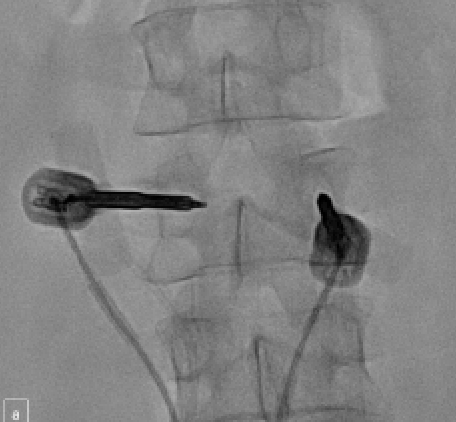

After undergoing conscious sedation with fentanyl and midazolam, the patient was placed prone on the fluoroscopic table. Scout images of the lumbar spine were obtained (Figure 3). From a bi-pedicular approach, 11G coaxial bone cannulas were advanced into the posterior aspect of the L3 vertebral body. A 13G bone biopsy cannula was used to obtain a core specimen from the lesion in order to diagnose the tumor type (Figure 4A). A drill-tipped stylet was advanced into the anterior margin of the vertebral body (Figure 4B) in order to select the appropriate OsteoCool RFA probe (Medtronic). Two 15-mm ablation probes were then inserted (Figure 5), and ablation was carried out over 11 minutes and 30 seconds to achieve an ablation zone of 23 × 18 mm.

After ablation, the needles were removed. A T-tip Kyphon curette (Medtronic) was used to create channels for balloon delivery and to facilitate better cement filling (Figure 6). Next, two 15-mm Kyphon balloons (Medtronic) were advanced into the vertebral body and inflated to optimize cement filling and provide height restoration (Figure 7). After the balloons were deflated and removed, cement cannulas were placed through the guide cannulas, and 6 mL of Xpede bone cement (Medtronic) were administered. All needles were removed, and hemostasis was achieved with manual compression. Final spot images of the lumbar spine were obtained (Figure 8). The patient was allowed to recover in the supine position for 3 hours in the post-procedural care unit prior to returning to his regular hospital bed.